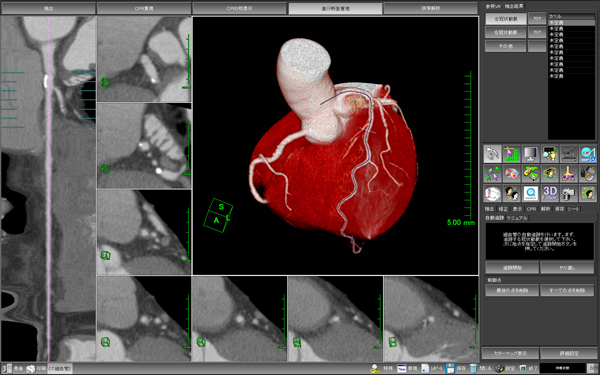

■使い易さを追求した「新・冠動脈解析ソフトウェア」

全自動解析の精度が大幅に向上し,画面レイアウトも読影及びレポーティング,画像保存など,目的に応じたレイアウトに改善されました。CPRとVR,Sliding MIPなどとの連携の強化や,画像保存が1クリックとなったことで,日常ルーチンで行なわれる冠動脈解析のワークフローを改善します。